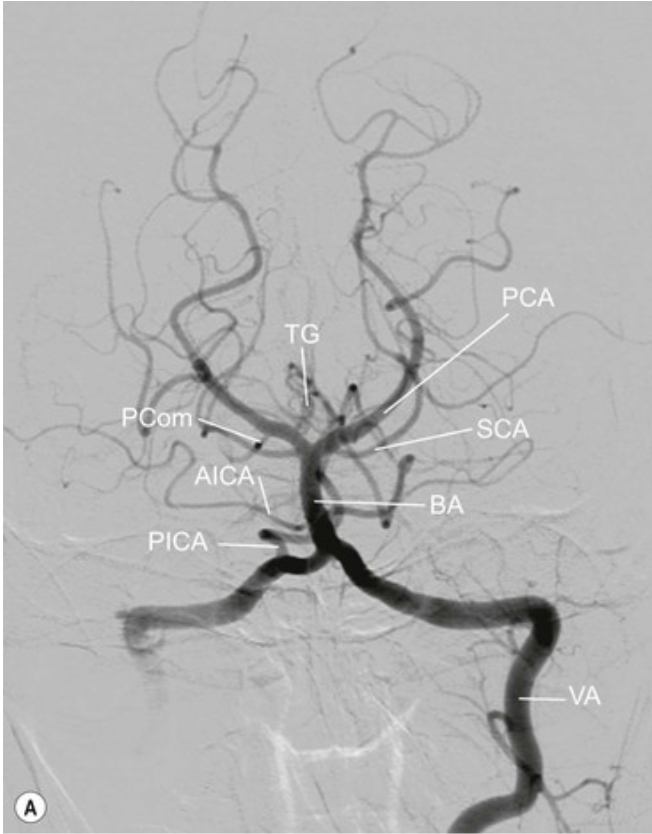

20.1 Patient presents with hemisensory loss and right homonymous hemianopia. Which vessel is affected?

A

PCA Contralateral

20.1 What lesion stroke right homonymous hemianopia and right hemisensory loss a) Posterior Cerebral b) Superior cerebellar c) Inferior cerebellar

PCA repeat